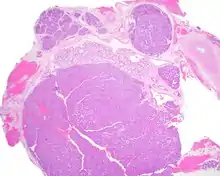

Canalicular adenoma is a type of growth that occurs in human salivary glands. It is a benign growth which occurs in the epithelial cells, and is typically arranged in columns of cells that form interconnecting cords. Canalicular adenoma is a very rare benign neoplasm; it constitutes about 1% of all salivary gland tumors and about 4% of all benign salivary gland tumors.[1][2]

Canalicular adenoma growths are usually small at the time they are noticed, with an average size of about 1.6 cm.[1] Their histologic appearance is very distinct, with a channel-like pattern between cords and ribbons; the pattern has been described as resembling a "string of pearls."

The growths often contain are often small bight squamous balls, or morules. They also tyipcally contain a well-developed supporting tissue - a fibrous stroma - which is rich in hyaluronic acid and chondroitin sulphate.[1] In a few cases, the growths may contain small calcium deposits or microliths. Although it is seldom necessary, a pathologist can confirm the existence of canalicular adenoma through immunohistochemistry studies, with the cells reacting with pancytokeratin, S100 protein and SOX10, with a delicate GFAP reaction around the periphery.[5][1][6][7] Although it is a benign tumor, a positive diagnosis of canalicular adenoma may be necessary to exclude the existence of other medical conditions such as a basal cell adenoma, pleomorphic adenoma, adenoid cystic carcinoma, and polymorphous adenocarcinoma.